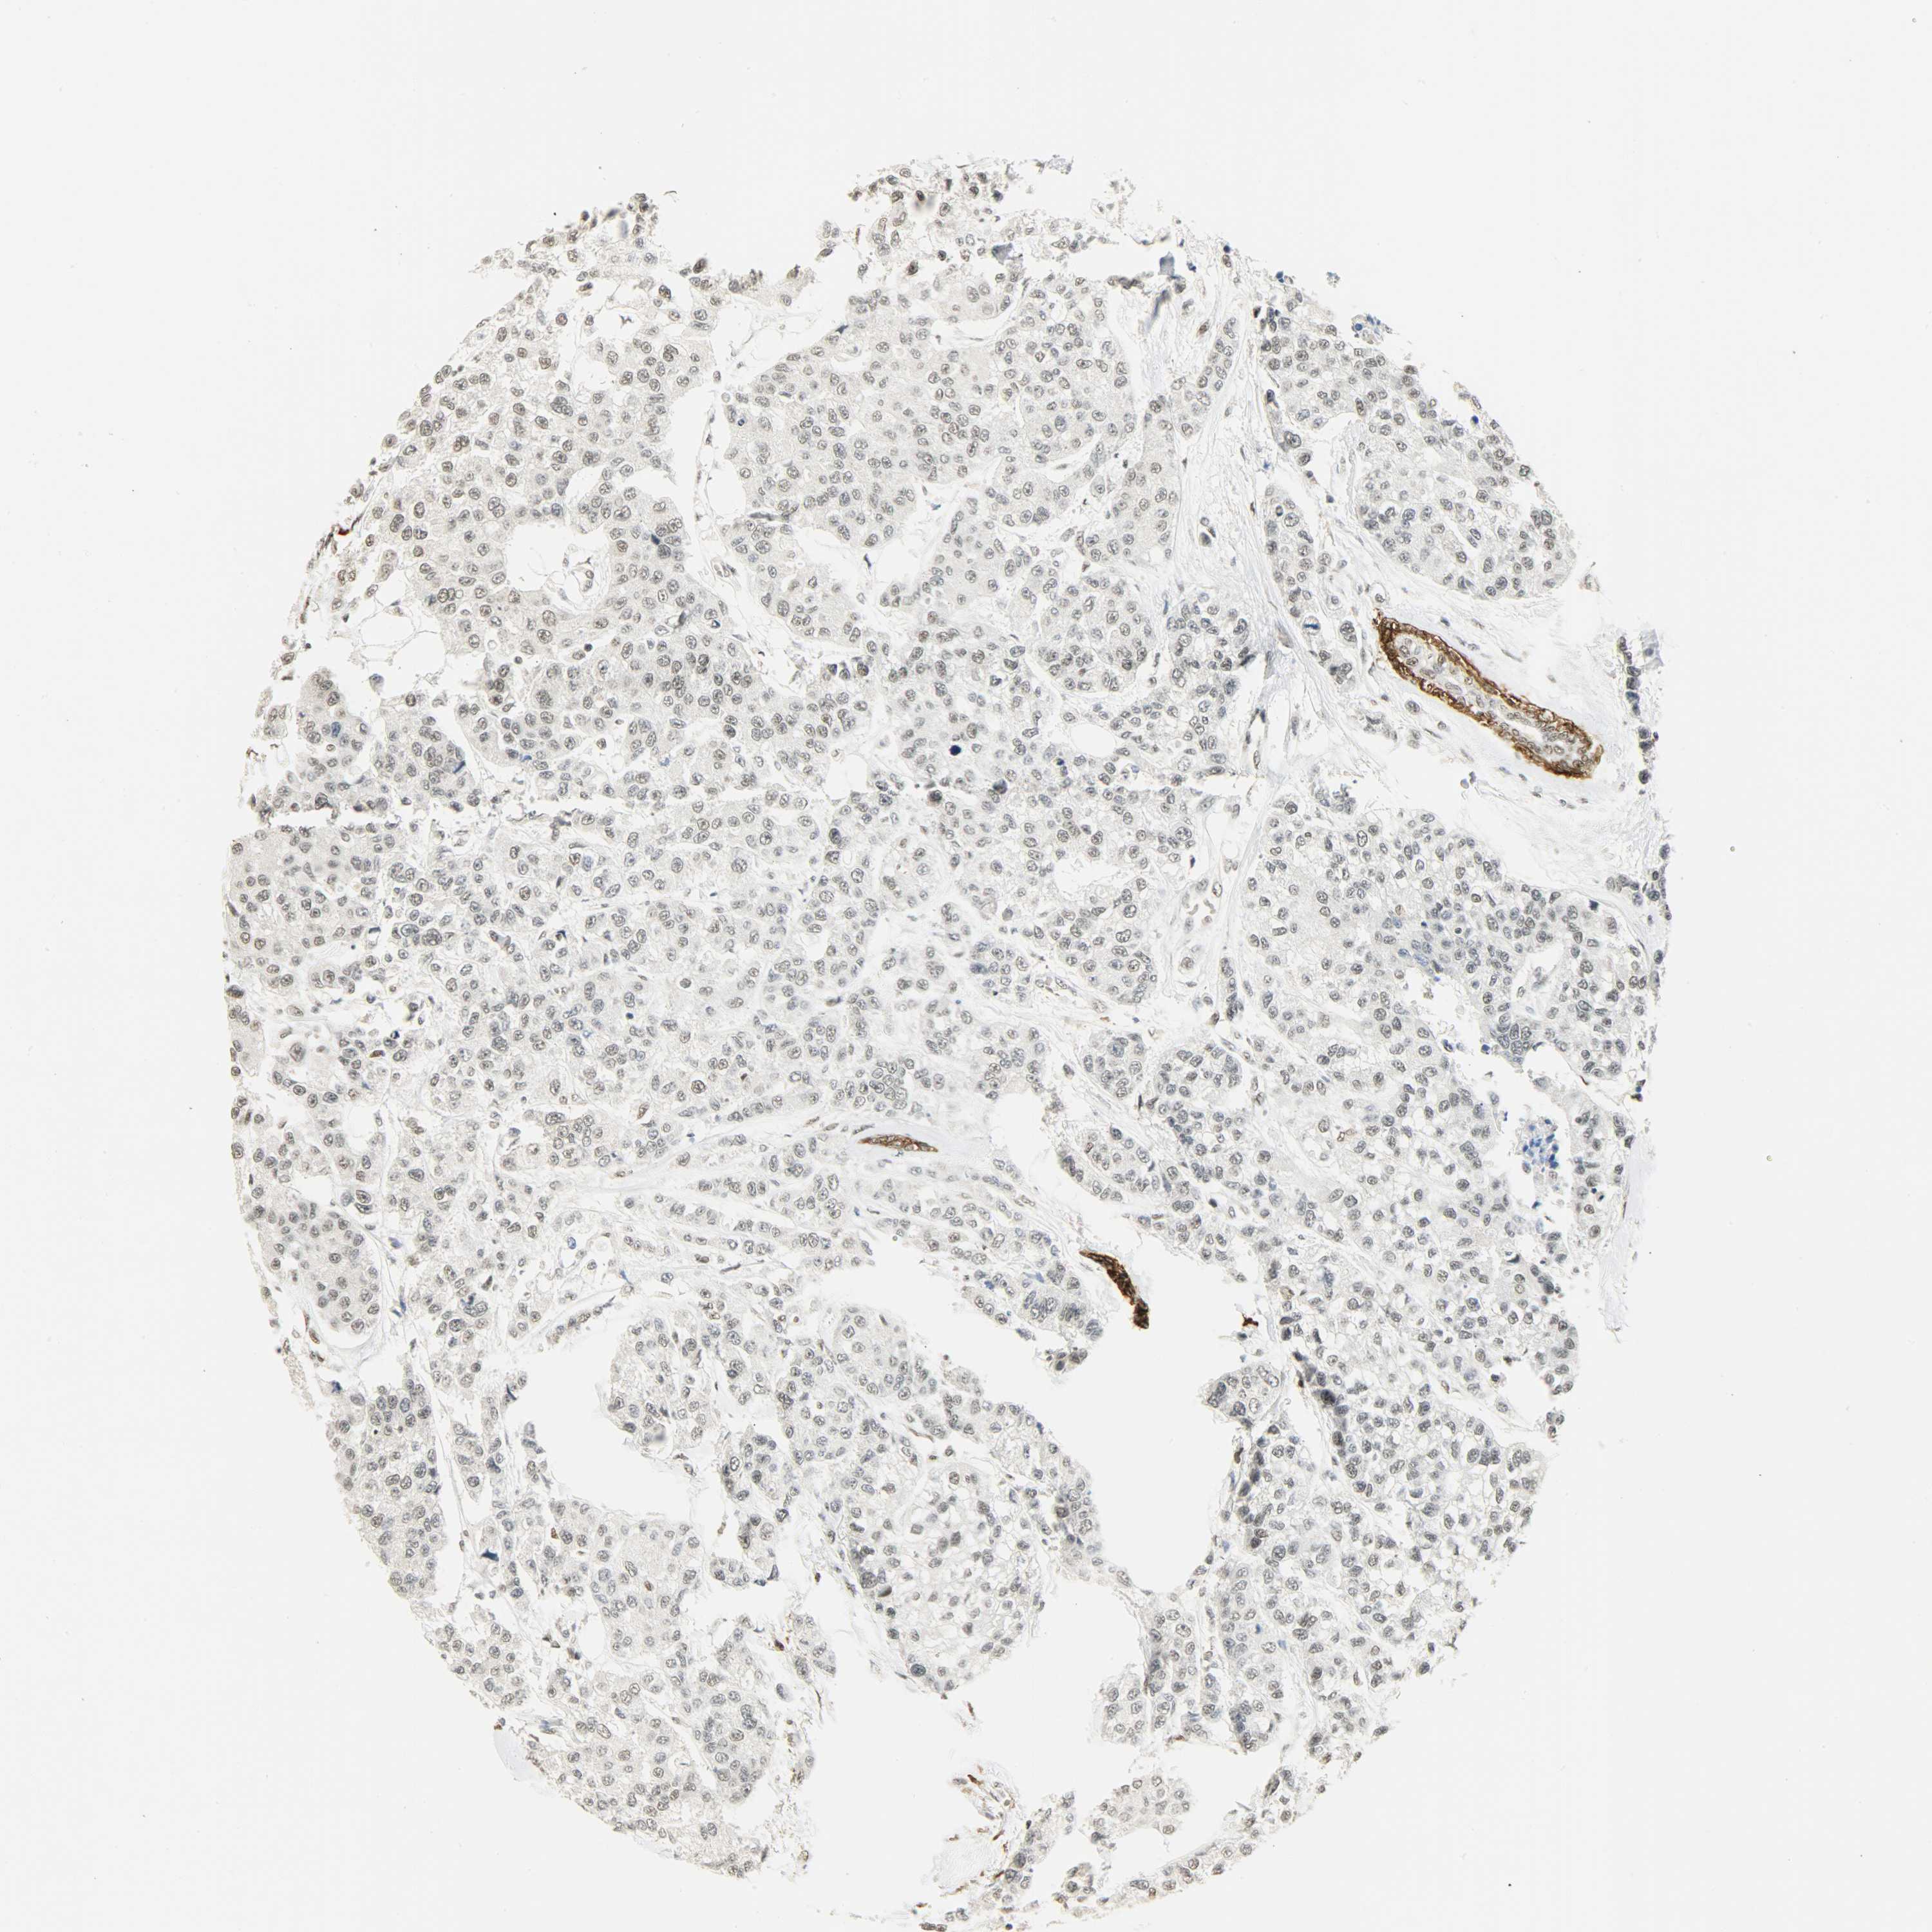

BRCA TCGA BRCA VALIDATION PROTEIN EXPRESSION

ANTIBODIES

AND

VALIDATION